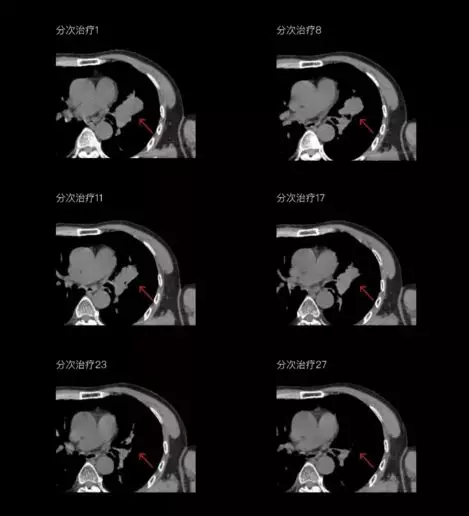

聯(lián)影CT-linac全程監(jiān)測治療過程病灶的變化,及時調(diào)整和優(yōu)化治療方案